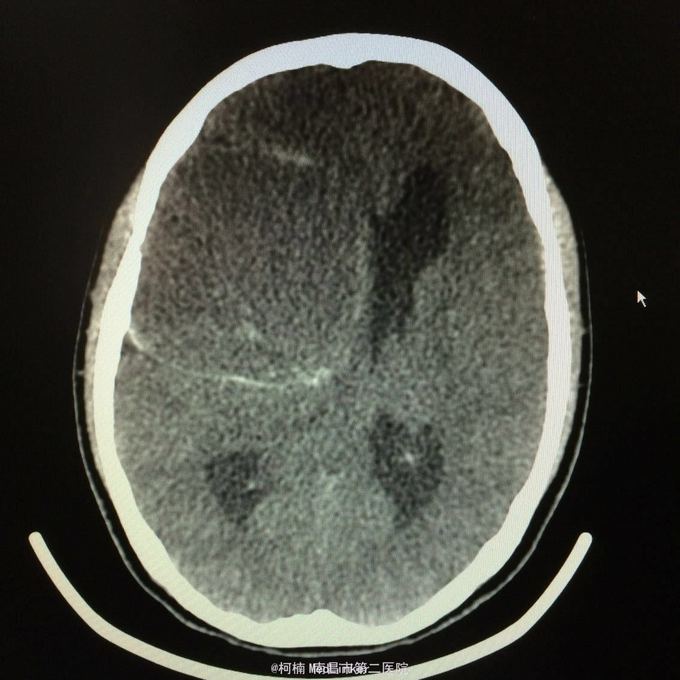

主诉:头痛2年,加重2月 病史:2年前无明显诱因出现头痛,主要为右侧额颞叶胀痛,近两个月来上述症状加重,遂至当地医院行头颅CT提示:右侧额颞叶类圆形异常信号,考虑脑膜瘤合并出血。

神经系统查体阴性 辅助检查:头颅CT提示右侧额颞骨板下肿物伴瘤卒中考虑脑外源性脑膜瘤

右侧额颞脑膜瘤 处理:全麻下行右侧额颞叶占位性病变切除术,术后病理提示:血管型脑膜瘤,WHO1级